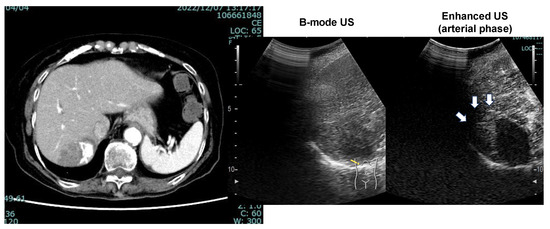

The patient’s liver function was maintained to Child-Pugh class A, and ATZ/BEV was started. The efficacy of the therapy became evident by the presence of SD after 2 courses of chemotherapy. Subsequently, a total of 12 courses of ATZ/BEV were completed, but contrast US and CT revealed that HCC recurrence was present, however, its status was within the SD category in the modified RECIST (Figure 7 right panel; contrast-enhanced CT arterial phase, left panel; contrast-enhanced US). Finally, RFA was performed on the right side of the S6 HCC (arrow in Figure 7, right panel) and ATZ/BEV combination therapy was restarted after the RFA procedure. A significant reduction in the levels of tumor markers, including AFP and DCP, was observed, and to date, the patient has not had any detectable recurrence of HCC (Figure 8).

Figure 7. CT image (arterial phase) and enhanced US after 12 courses of ATZ/BEV therapy. Left panel: CT image showing the disappearance of lipiodol and the appearance of arterial flow on the right side of the HCC. Right panel: Contrast-enhanced ultrasound revealing arterial flow in the arterial phase and a defect in the Kupffer phase.